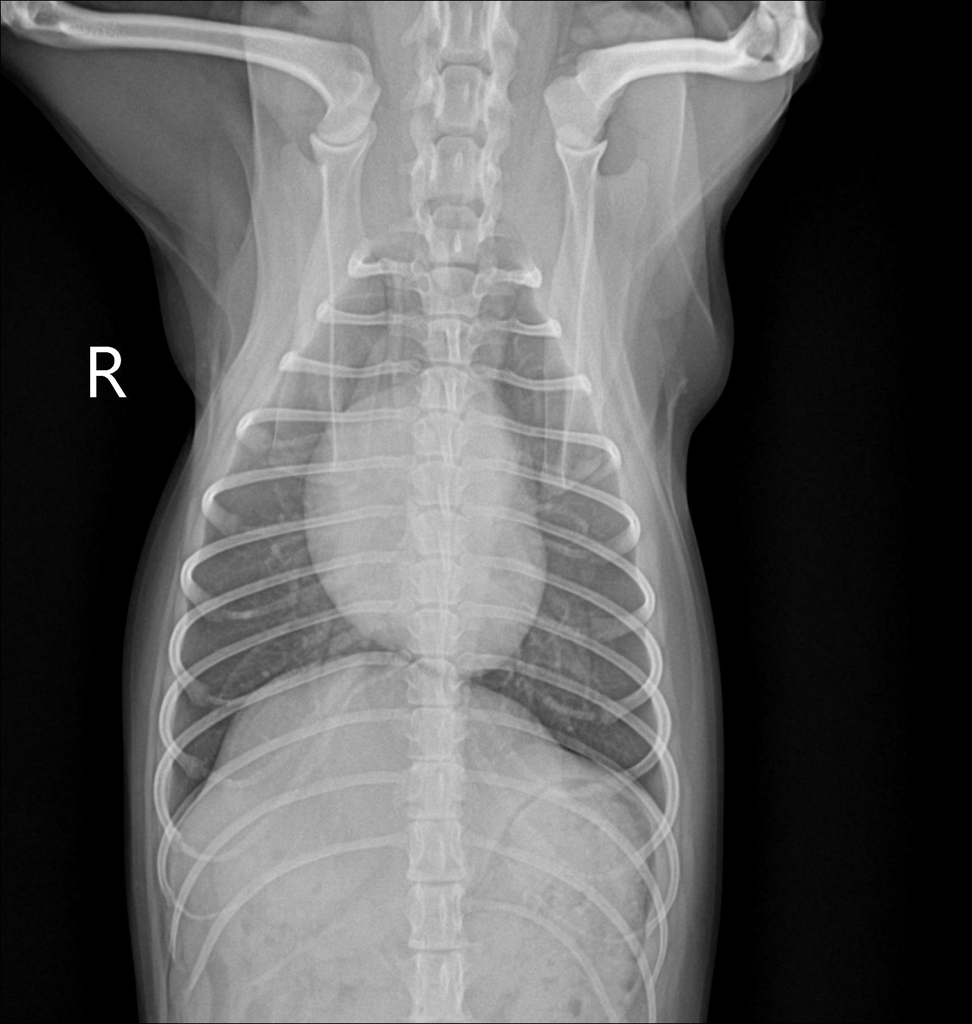

우리 강아지 디스크 일까요..?움직이지 않아요

평소랑 달리 움직이없고 헥헥 거리며 끙끙 앓아요 사진상으로 디스크 의심갈만한 문제가 없어보인다는데 전문가들의 의견이 궁금합니다 ㅜ ㅜ

방사선 만으로는 디스크를 확진할 수 없습니다.

그외 신경검사인 심부통증 반응과 자세반응 등 신경계 검사와 확진을 위해서는 CT촬영과 MRI 촬영이 필요합니다.

화살표를 해둔 부분의 디스크 공간이 좁아 보이는 양상이 경미하게 관찰되어 의심해볼만한 가능성은 있으나 디스크는 엑스레이 사진으로 진단되는 질환이 아니기에 다른 검사 결과에서 디스크를 강력히 의심할만하다면 MRI 검사가 추천됩니다.

반복된 촬영에서 재현성도 확보되어 증상이 지속된다면 이 사진을 근거로 MRI 촬영을 해봐야 하는 사항으로 판단됩니다.